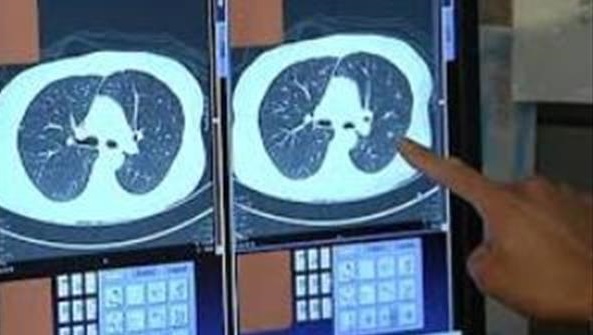

خودش رفت پیش دکتر و شرح حالم رو بدون حضور من داد و دکتر هم برام سی تی اسکن نوشت. دستور دکتر رو داد بهم و گفت:" بلند شو بیا اینجا ! این نوار زردو می بینی؟ همینو برو میرسی به سی تی اسکن."

تمام دستگاه خیس بود از مواد ضد عفونی کننده. چشمامو بستم قطره ای از این مواد نریزه تو چشمم ، چون خودش معلوم نبود چی باشه؟! بالاخره بعد از چند بار نفس عمیق کشیدن و اتمام کار رفتم جلوی اتاق دکتر که دیدم دو سه نفر دکتر جوان و احتمالا دانشجو نشسته اند و در حال مشورت اند.

چند دقیقه ای صبر کردم و جواب سی تی اسکن آمد . دکتر که خودش هم انگار مریض یا بی حال بود ، در حالیکه دستش رو روی سرش گرفته بود، یه نگاهی به صفحه ی مانیتورش انداخت و بعد از بالا و پایین کردن تصویر گفت: "منفیه ، مشکلی نداری برو. "